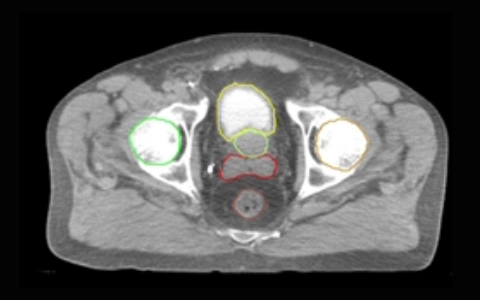

‒Competently outline the target volumes (in prostate patients only) and organs at risk in accordance with RT departmental protocols for prostate and head and neck cancers.